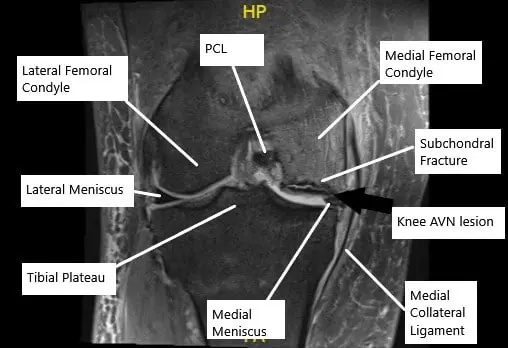

MRI of the knee in the coronal section showing AVN lesion along with subchondral fracture in the medial femoral condyle.

The primary cause of AVN is the disruption of blood supply to the bone, leading to bone death (infarction). In the knee, AVN often affects the medial femoral condyle, which is the inner part of the thigh bone. The lack of blood flow prevents the bone from receiving essential nutrients and oxygen, causing the bone tissue to die and potentially collapse. While many cases of knee AVN are idiopathic (no known cause), risk factors include:

The knee joint is the largest weight-bearing joint in the body, consisting of the femur (thigh bone), tibia (shin bone), and patella (kneecap). The ends of these bones are covered by articular cartilage, and just beneath it lies the subchondral bone. AVN affects this subchondral bone, often starting in the medial femoral condyle, and can lead to joint collapse if untreated.

- MRI: MRI is the most sensitive tool for diagnosing AVN, revealing changes in bone structure, subchondral fractures, and early signs of bone death.